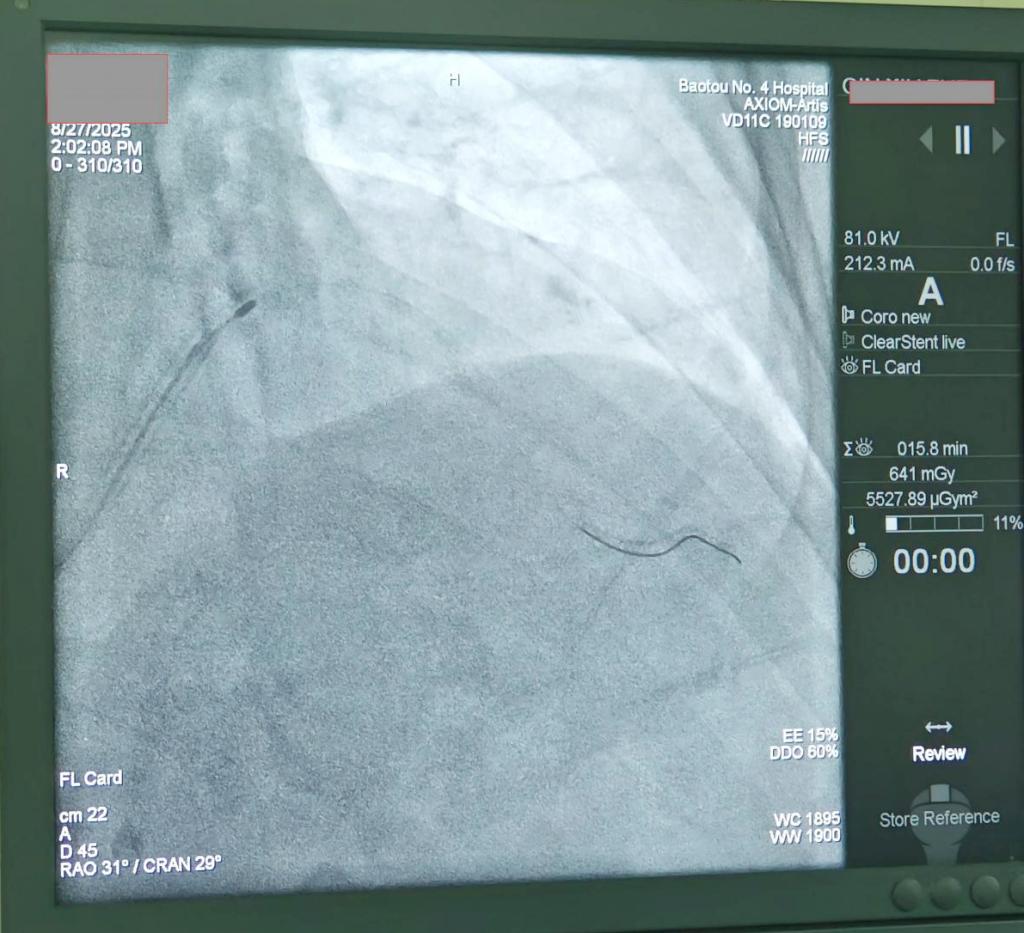

旋磨导管进入冠脉时图像

手术当日,手术团队操作娴熟、配合默契,直径仅1.25毫米的金刚石涂层旋磨头以每分钟近14万转的高速旋转,如同精密的“隧道掘进机”,一点点地将患者冠脉内坚硬的钙化斑块研磨成比红细胞还小的微颗粒,被人体血液循环安全吸收。旋磨过程顺利,成功为后续治疗开辟了通道。随后,团队成功植入两枚支架,术后患者血管血流通畅,胸痛症状显著缓解,恢复情况良好。